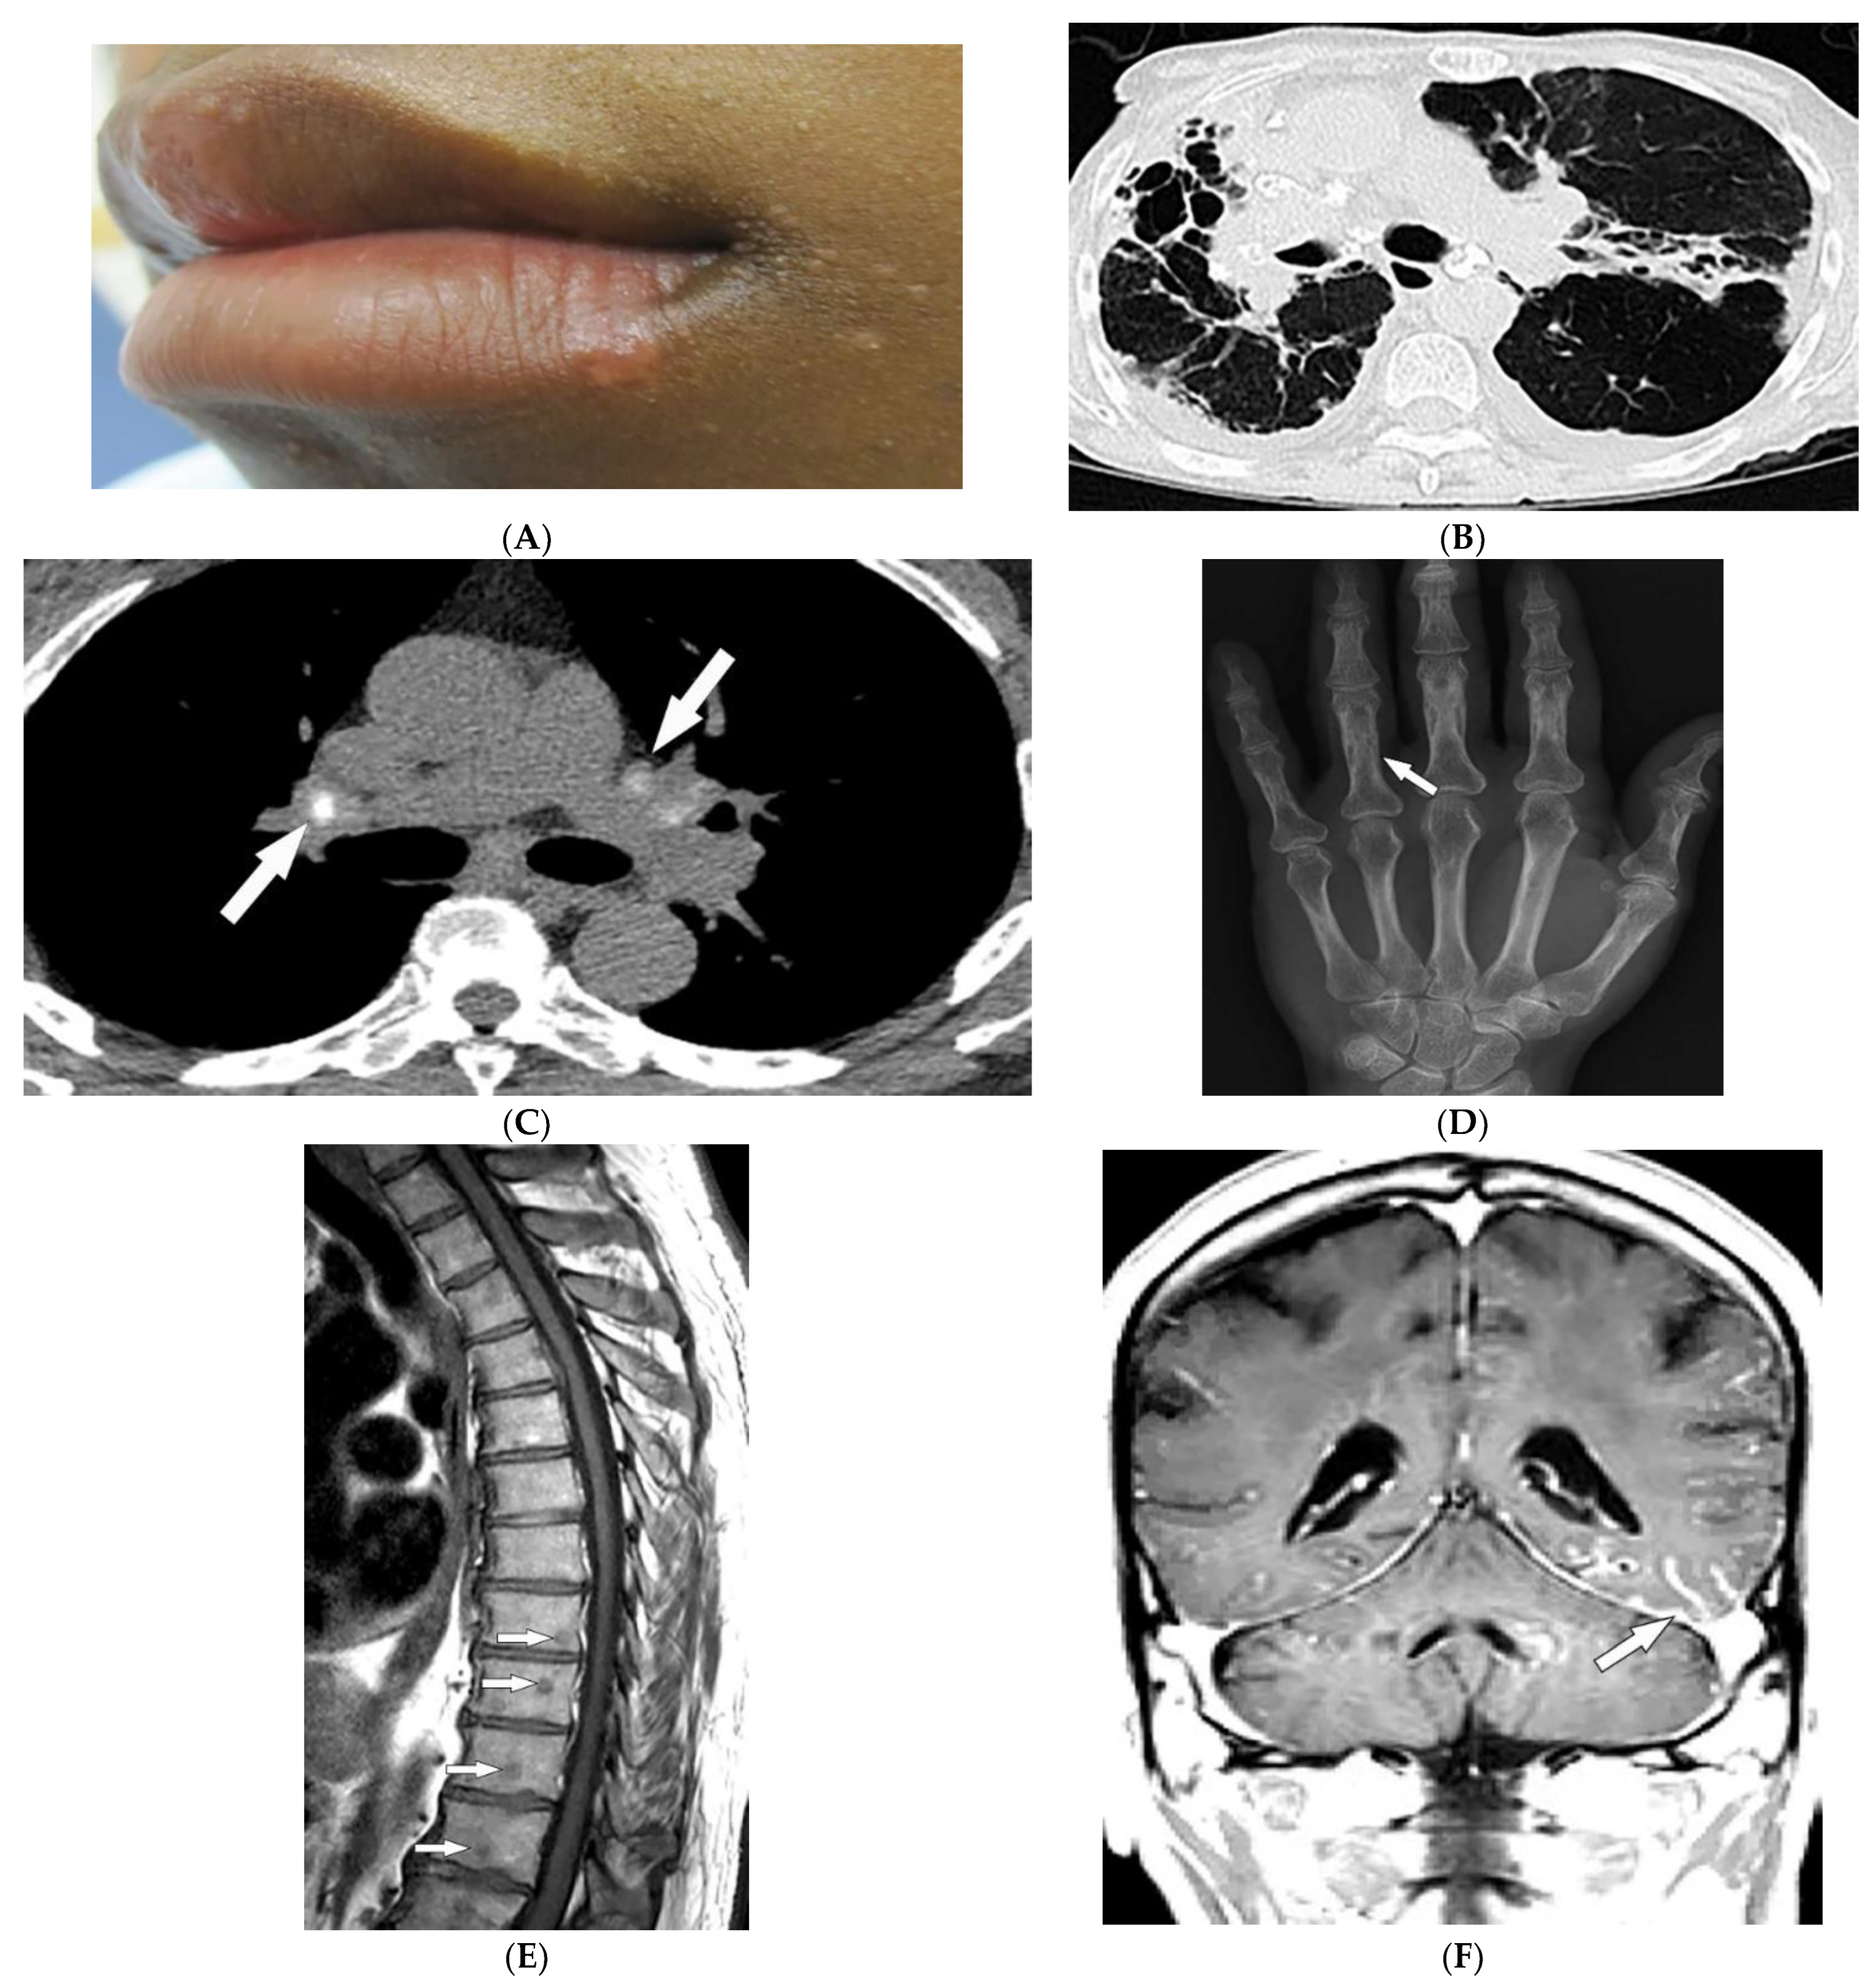

3.6. Hereditary Hemorrhagic Telangiectasia

| Hereditary hemorrhagic telangiectasia | Recurrent epistaxis Multiple telangiectasias Arteriovenous malformations | Bilateral well-defined lung opacities with lobulated shapes Ground-glass nodule |